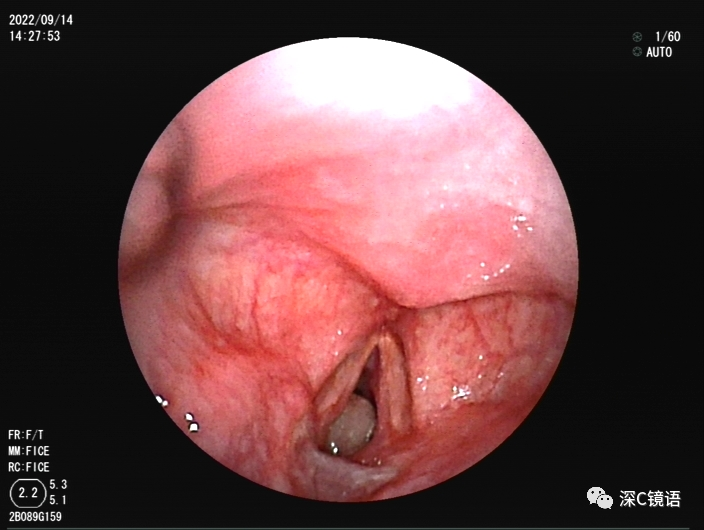

医疗方面:目前,我科室能开展呼吸内镜相关诊断与治疗技术,具体如下:诊断技术包括经支气管镜冲洗术、灌洗术、刷检术、活检术、针吸活检术、环形超声以及内科胸腔镜等;治疗技术包括球囊扩张术、支架植入术、高频电凝术、高频电圈套治疗、激光治疗、冷冻治疗、局部注药治疗等。秉承“患者所需,医者所为”的宗旨,为肺部感染、肿瘤、气道异物、不明原因胸腔积液,尤其是气道结核的患者,提供综合诊治方案。